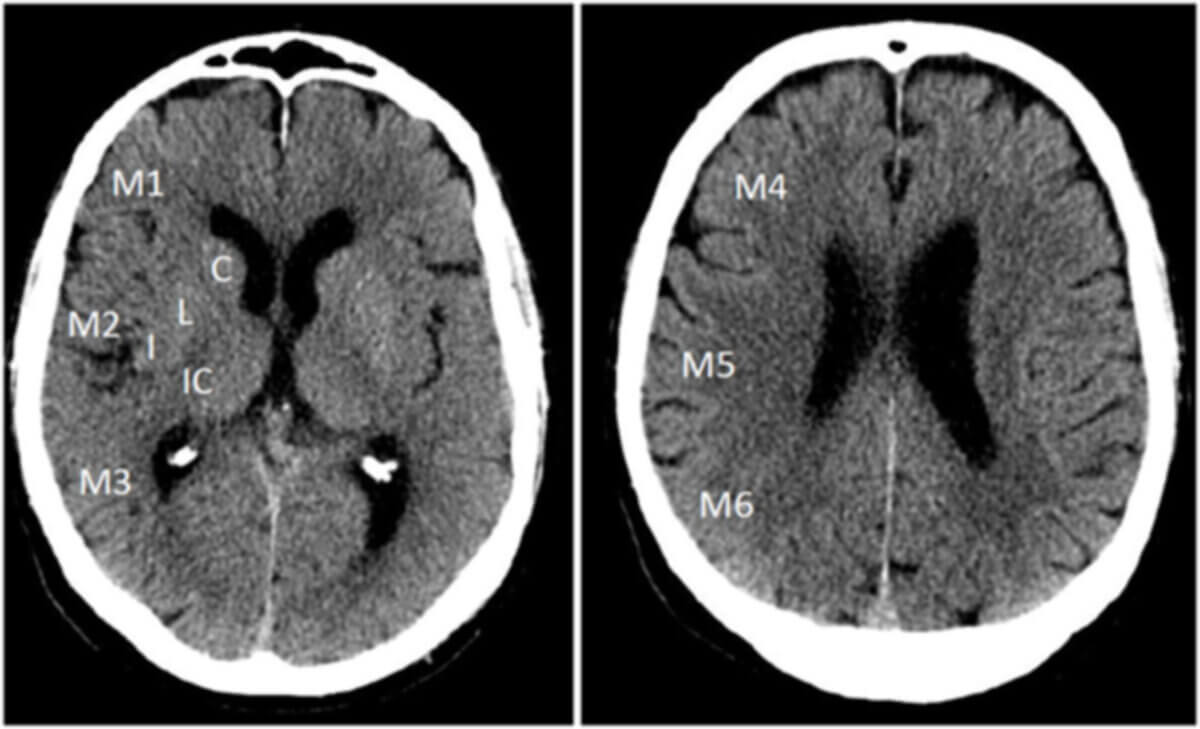

Das Versorgungsgebiet der ACM wird in zehn gleich gewichtete Territorien unterteilt. Unterschieden werden sechs kortikale Areale (M1–M6) sowie vier tiefere Strukturen (Nucleus caudatus, Putamen, Capsula interna und Inselregion).

ASPECTS-Zonen auf NCCT[2]